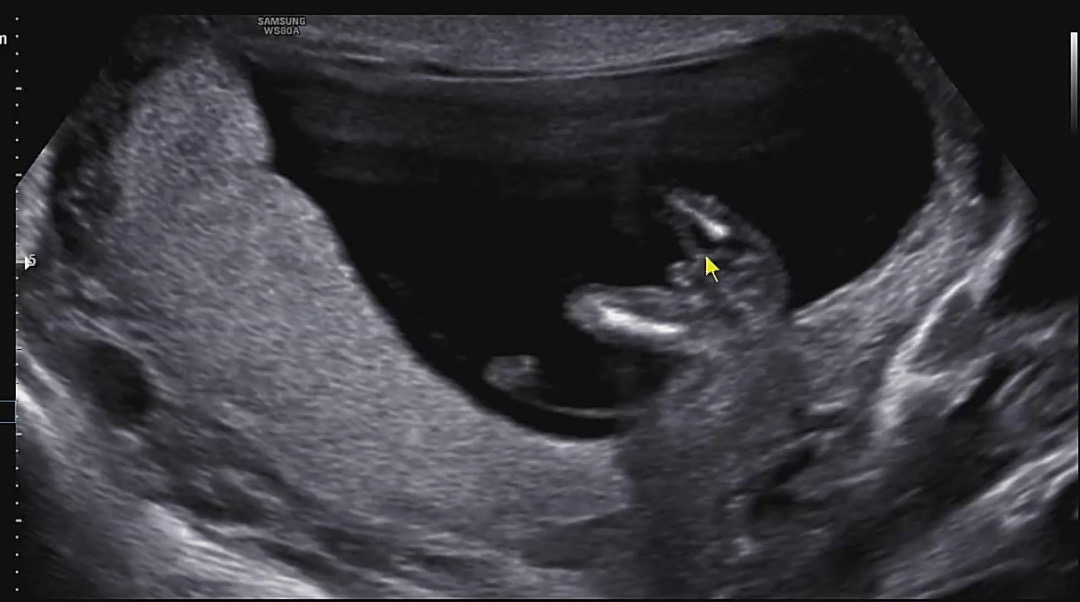

13주 성별

빼박 아들이겠져..?ㅎㅎㅎ